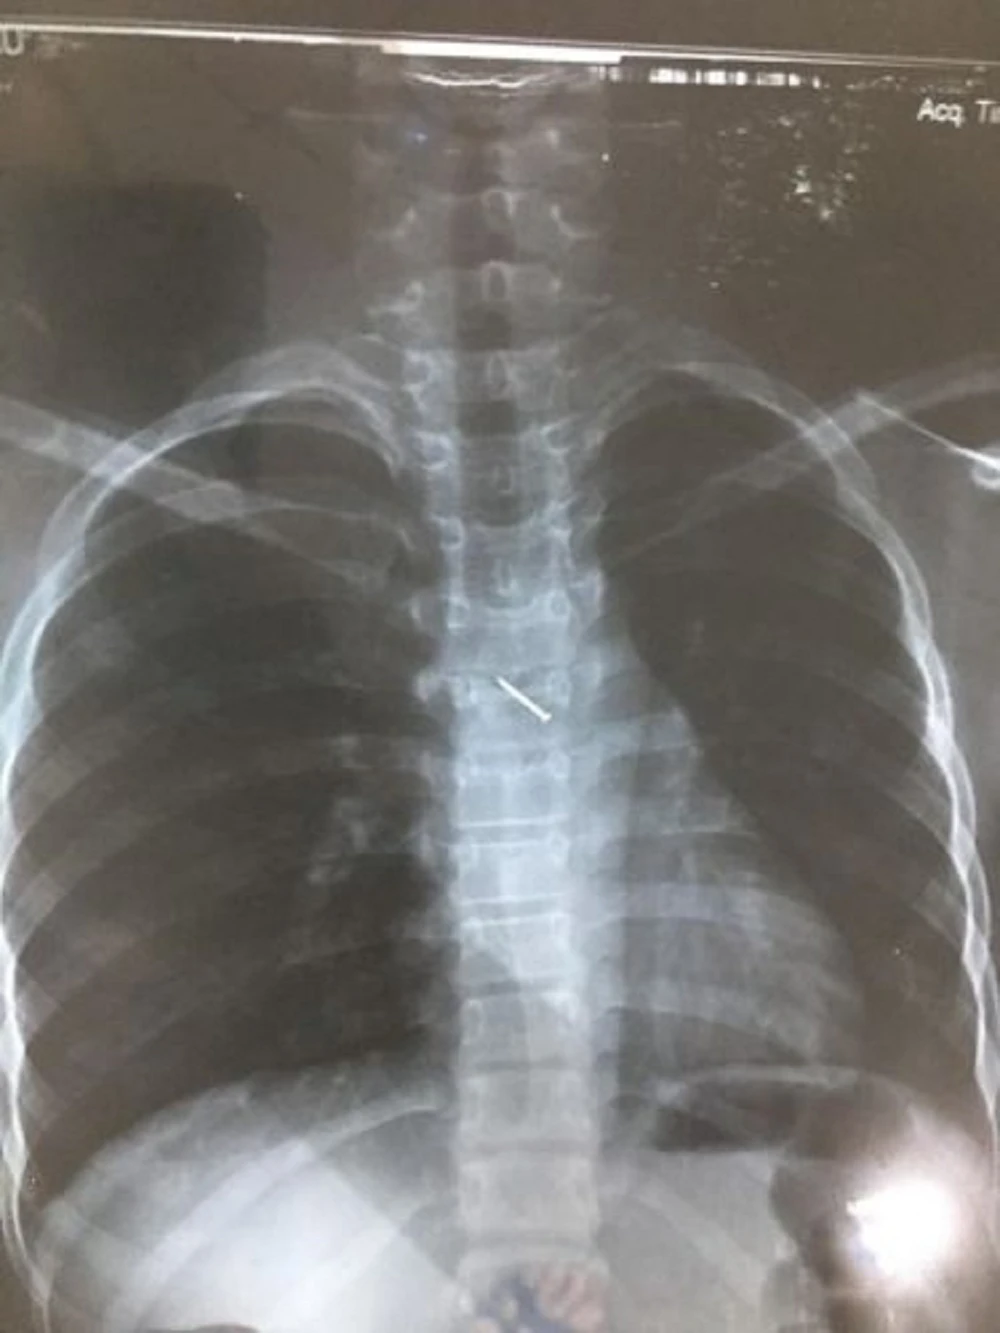

Sau sự cố, bé ho sặc sụa, khạc ra máu, nôn nhiều nên được người nhà đưa đến BV đa khoa Mộc Châu (Sơn La) khám. Tại đây, qua chụp X-quang các bác sĩ xác định lồng ngực bệnh nhân có dị vật hình đinh ghim. Bệnh nhân được chuyển tới BV Nhi Trung ương để theo dõi và tiếp tục điều trị.

Tại BV Nhi Trung ương, hình ảnh chụp X-quang cho thấy có dị vật là một chiếc đinh ghim dài khoảng 1,5 cm nằm ở vị trí thành ngực của bệnh nhân. Các bác sĩ đã hội chẩn và quyết định phẫu thuật nội soi lấy dị vật.